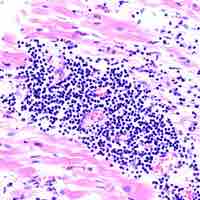

The lymphatic system houses large populations of immune cells which are released upon detection of a pathogen.

Cell-mediated immunity involves cytotoxic T cells recognizing infected cells and bringing about their destruction.